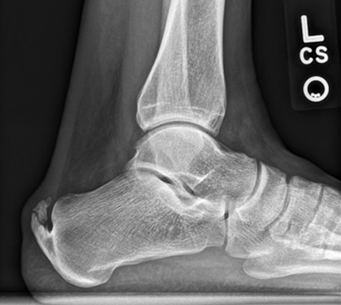

Haglund’s deformity

A bony prominence at the back of the heel

Can worsen insertional Achilles pain

Symptoms may be aggravated by stiff-backed footwear

Occurs where the tendon attaches to the heel bone

Often associated with bony irritation at the heel